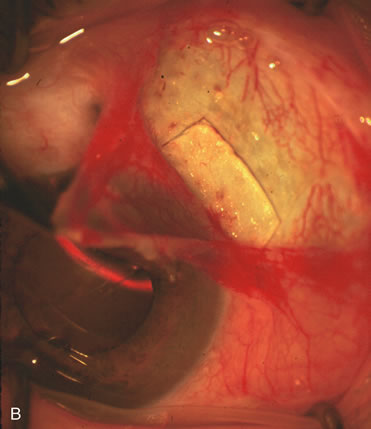

Nonpenetrating procedures as they exist today generally decrease postoperative complications but do not reduce IOP as successfully as trabeculectomy.140 The success rate also appears to be highly dependent on race, length of topical antiglaucoma therapy, and prior ocular surgery.141,142 Deep sclerectomy combined with phacoemulsification results in an IOP reduction similar to phacotrabeculectomy at one year with comparable visual outcome.143 Phacoviscocanalostomy lowers IOP by approximately 33%144 through either a one- or two-site approach145 (Fig. 4). Nonpenetrating procedures are in evolution, and their place in long-term glaucoma care is still unclear.

Fig. 4. Viscocanalostomy with deep sclerectomy and phacoemulsification. Nonpenetrating filtration procedures (NPFS) may be combined with phacoemulsification. Patients with mild disc damage and a history of limited topical drug therapy are the best candidates. Patients who require an IOP in the low teens are not good candidates for NPFS. By definition, NPFS is designed to lower IOP without penetrating into the anterior chamber, thereby avoiding the complications associated with trabeculectomy. Viscocanalostomy is intended to allow aqueous to percolate through a trabeculodescemetic membrane into a subscleral cavern created by the deep sclerectomy. The aqueous diffuses from the cavern into the dilated ostia of Schlemm's canal and into the episcleral venous plexus. A. Fashion a uniform 300-micron superficial scleral flap 1 mm into clear cornea. B. Construct a second 600-micron deep flap that facilitates the unroofing of Schlemm's canal, seen as the darker area. C. Use viscoelastic to dilate the ostia of Schlemm's canal. The major problem with viscocanalostomy is the eventual closure of the ostium decreasing flow to the episcleral plexus. D. Dissect the deep flap anteriorly into clear cornea creating the trabeculodescemetic membrane. This membrane is clearly seen between the scleral spur and the bend of the deep flap. The integrity of this membrane ensures the nonpenetrating portion of the surgery. Another problem with NPFS is the eventual fibrosis of this initially transparent membrane requiring goniopuncture. E. Deep sclerectomy gets its name from removal of the deep flap. Removal of this flap creates the potential subscleral space for accumulation of aqueous before it enters Schlemm's canal and exits the episcleral venous plexus. After removal of the deep flap, the superficial flap is sutured into place and conjunctiva closed. Approximately half of these procedures develop a shallow bleb.